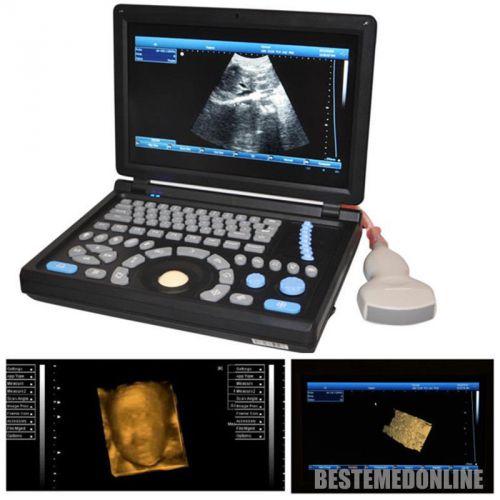

3D PC Platform Full Digital Laptop Ultrasound Scanner+ Convex &Linear BEST CHOIC

HOT HOT HOT! Digital Ultrasound Scanner 4-frequency Convex +Linear probes +3D

3D Digital Ultrasound Scanner +Convex TV 2 probes Optional 2 probes+3 years warr

ONLY 1-MONTH SALE!!! Digital Laptop Ultrasound Scanner Diagnostic + Linear 3D

NEW Full Digital TFT LCD Ultrasound Scanner High-resolution (built-in 3D) CONVEX

FULL DIGITAL Portable Ultrasound Scanner 3 probes "Convex,Linear,TV" +3D GOOD+++

3D Full-digital Ultrasound scanner machine with 3.5MHz R60 convex +2 USB Ports

Hot 3D Full-digital Ultrasound scanner machine W CONVEX +2 connectors+2USB ports

3D 10.1" Full Digital Laptop Ultrasound Scanner Machine +Micro-convex Probe CE

in 3D Full Digital Laptop Ultrasound Scanner (PC) with convex probe Free Ship

NEW 10.4" 3D PC platform Full Digital Laptop Ultrasound Scanner+ 3.5Convex Probe

+Aluminum box Full Digital 3D PC LAPTOP Ultrasound Scanner vaginal NEW